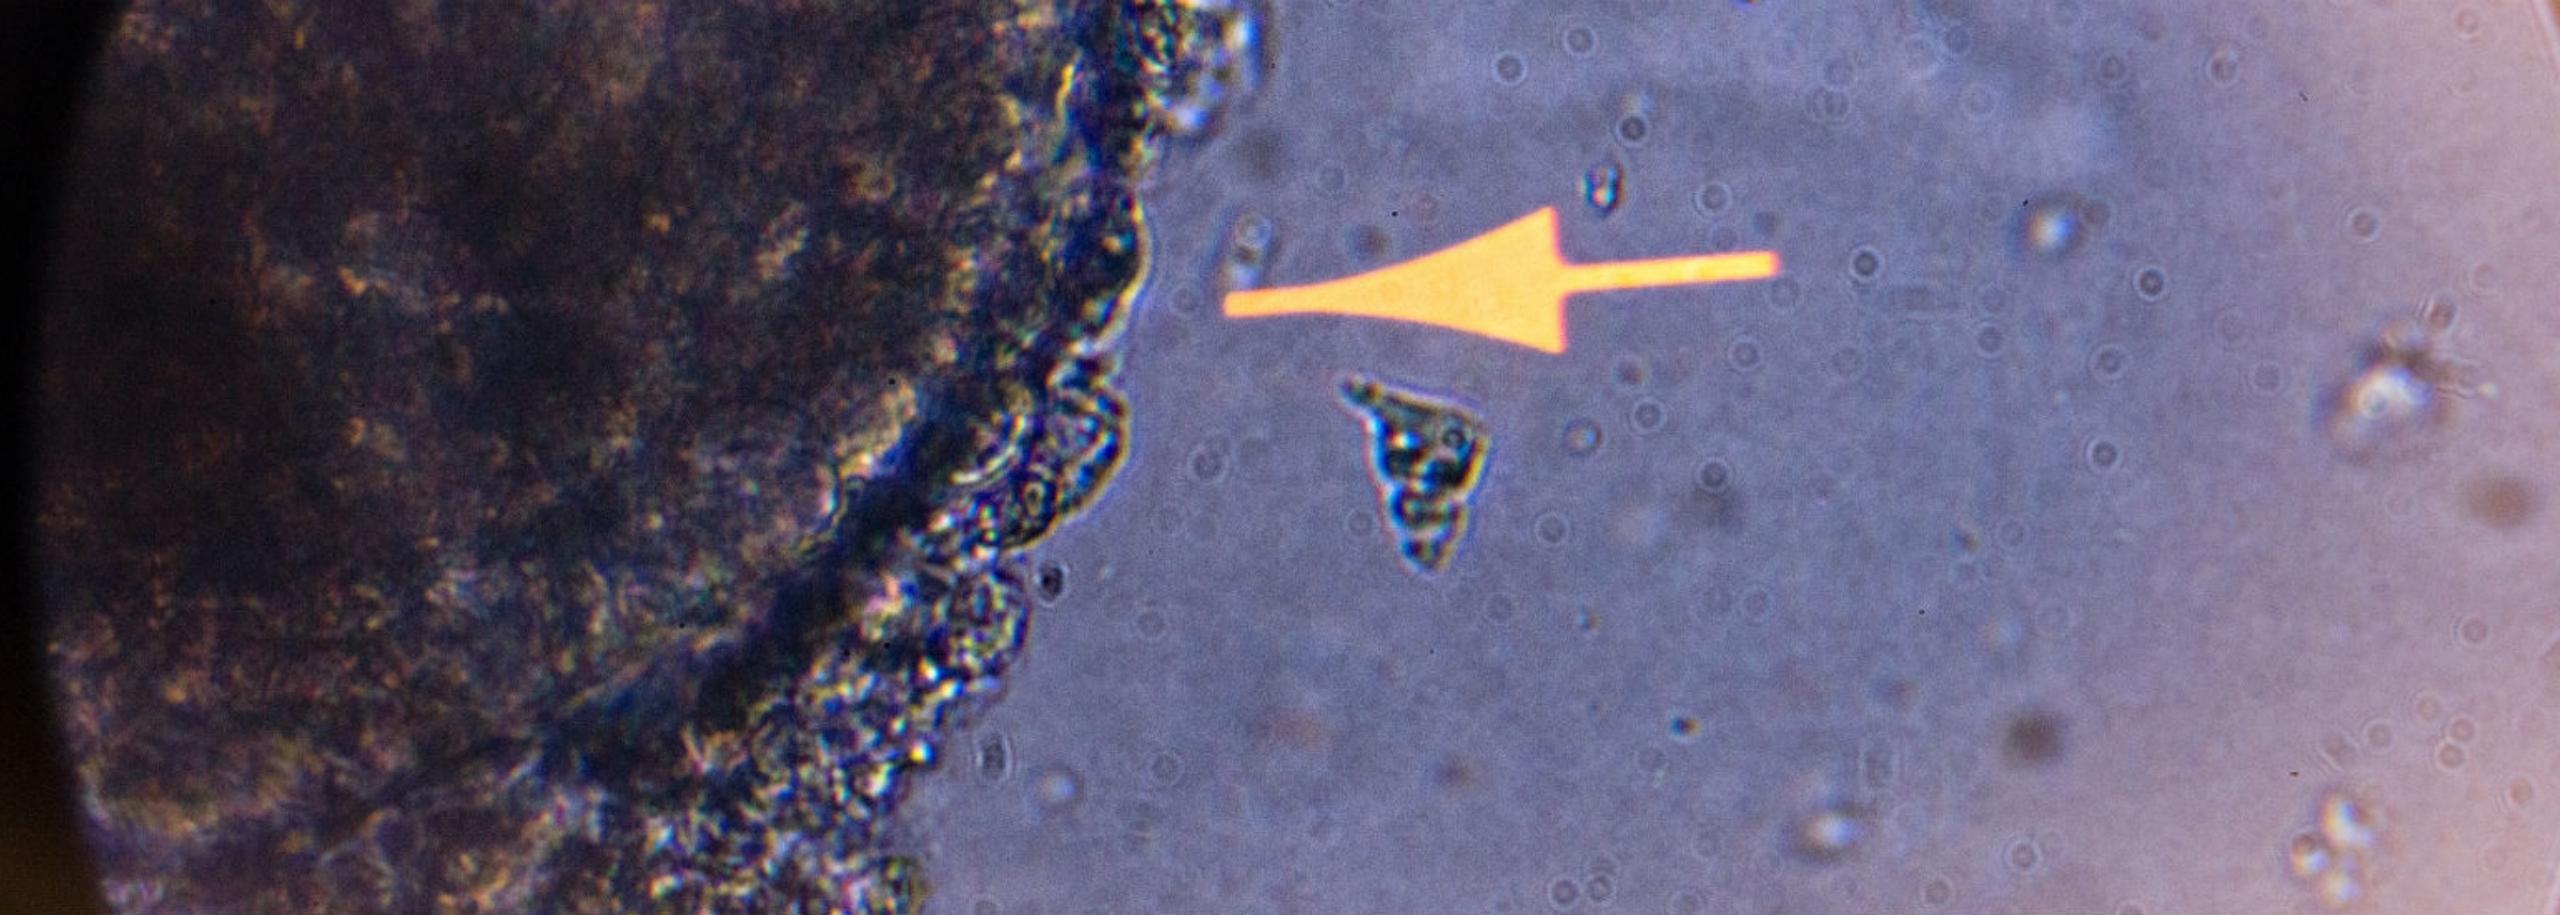

“Vanuit mijn promotieonderzoek werkte ik al met menselijke cellen. En dat heb ik doorgezet in de rest van mijn onderzoek. Maar daarin liep ik wel tegen wat beperkingen op. Cellen die we gebruiken voor virusonderzoek zijn namelijk cellen die goed in het lab kunnen groeien, bijvoorbeeld kankercellen, of cellen afkomstig van apen, want apen worden veel gebruikt in virusonderzoek. Maar dergelijke cellen die hebben niet de eigenschappen van gezonde menselijke cellen. Daarom waren er een aantal vragen die wij niet konden beantwoorden en was ik op zoek naar andere modellen. En toen heb ik een bewuste keuze gemaakt om dit niet met proefdieren te doen. Dit was zowel een ethische als een wetenschappelijke keuze.

Ik hoorde over onderzoeker Hans Clevers, die darm-organoids had gebruikt in onderzoek. Daar is het idee geboren om organoids te gebruiken voor virusonderzoek. Toen moesten we nog wel geld bij elkaar halen, en dit heeft best wel lang geduurd, van 2010 tot 2014 ongeveer. Toen startte mijn eerste Europese onderzoeksnetwerk, en kwamen we in aanraking met jullie en via jullie met het ZonMw-programma Meer Kennis met Minder Dieren. Jullie waren, net als ik, enthousiast over mijn onderzoek en we besloten samen te werken. Dankzij jullie hadden wij genoeg financiering om de organoids voor virusonderzoek verder uit te bouwen.”

“Tegelijkertijd geeft COVID ook een mooi moment voor echte innovatie. We zien duidelijk een toename van het gebruik van organoids binnen het onderzoek naar COVID. En er worden ook steeds meer organoids ontwikkeld voor virussen waarvoor proefdieronderzoek niet goed werkt, zoals virussen die diarree veroorzaken. Ontwikkelingen op het gebied van organoids voor virusonderzoek gaan ontzettend snel. Maar nog niet snel genoeg voor een proefdierverbod voor virusonderzoek, want de ontwikkeling van vaccins is moeilijk zonder proefdieren. Ik weet nog niet hoe je dat met organoids zou moeten doen. Maar er is steeds meer mogelijk met organoids, en inmiddels kun je ook het een deel van immuunsysteem nabootsen in deze modellen.”